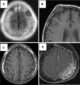

Metastasis to dura